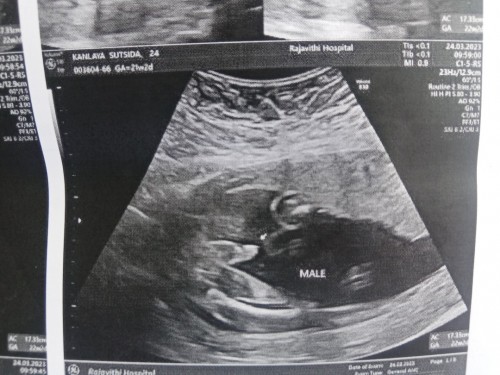

ตอนนี้ท้องได้ 5 เดือนแล้วค่ะ เพิ่งจะไปอัลตร้าซาวด์ตามที่หมอนัดมา

อยากสอบถามแม่ๆว่าตรงที่มีลูกศรคืออวัยวะเพศน้องใช่ไหมคะ